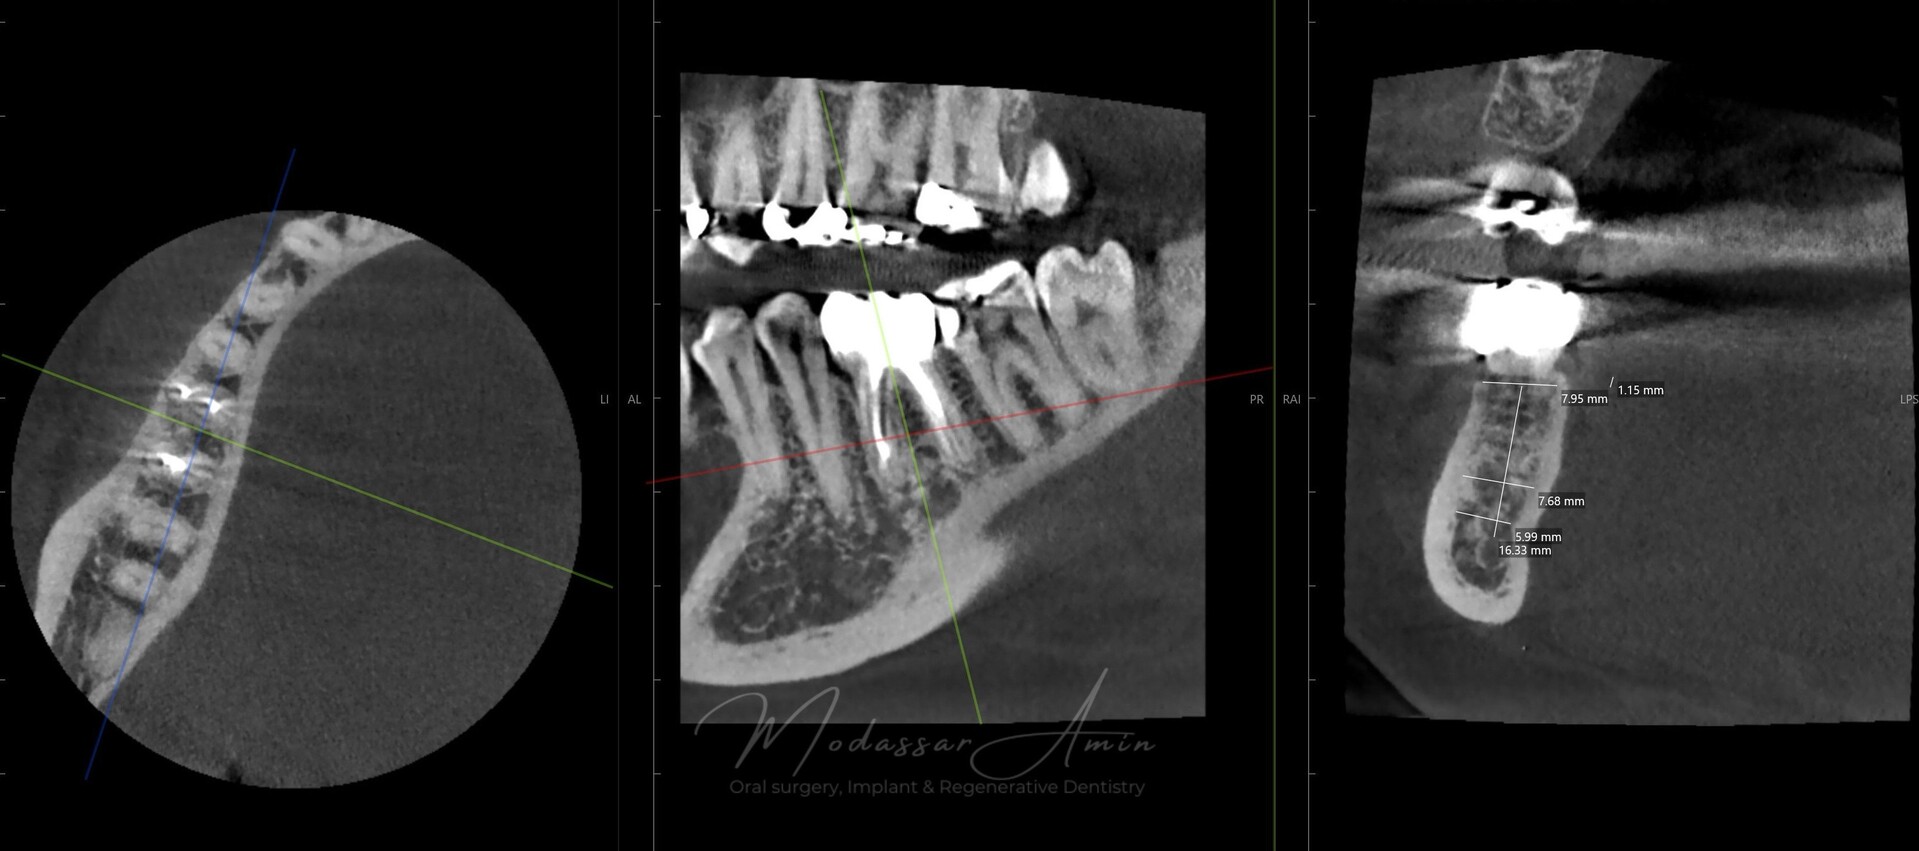

"Pasienten presenterte med tann 46 som ikke kunne bevares grunnet en dyptgående infraksjon inn i furkasjonen. Forholdene lå til rette for en immediate implantatbehandling. Ved hjelp av Versah osseodensifikasjonsbor ble det interradikulære beinet ekspandert på en skånsom og forutsigbar måte, noe som ga høy primærstabilitet (>40 Ncm) til tross for en lokal bendefekt apikalt mesialt etter kronisk apikal periodontitt. Den gode stabiliteten muliggjorde bruk av SSA (Sealing Socket Abutment) for forsegling. På grunn av tynn bløtvevsfenotype bukkalt ble behandlingen supplert med bindevevstransplantat (CTG)"

CBCT röntgen